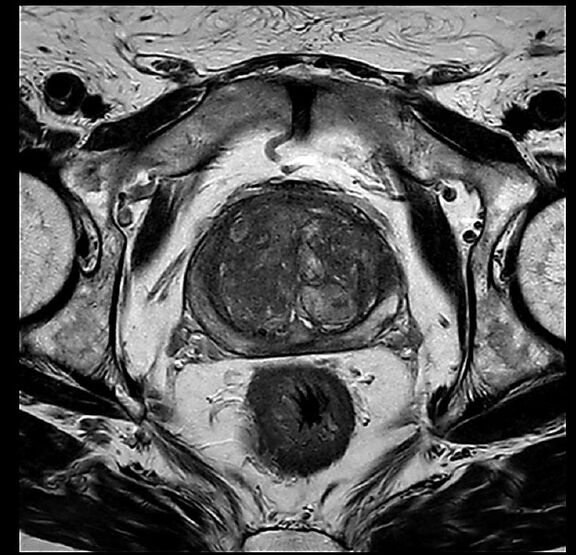

Beispiele von MRT-Prostata Aufnahmen